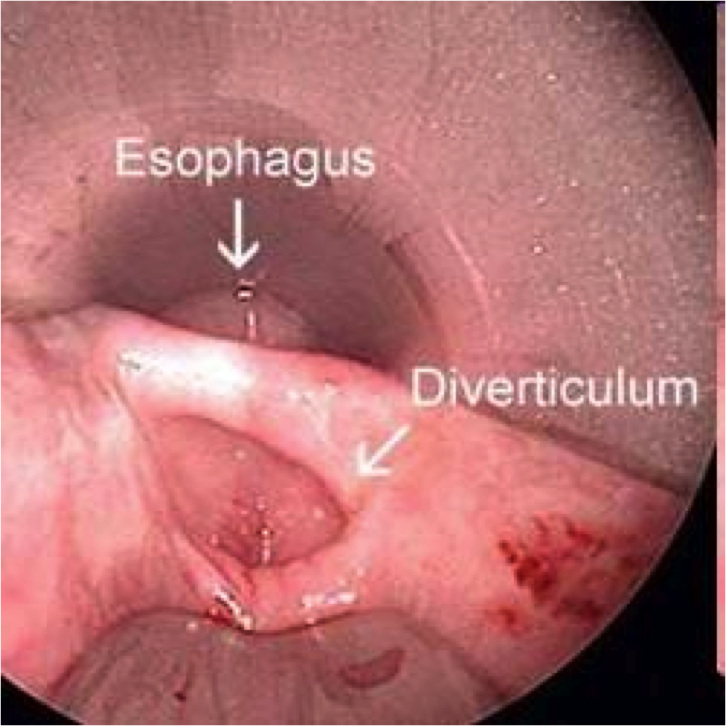

Esophageal diverticula

Outpouchings of the esophageal wall

- True = all layers, including muscle

- False = mucosa & submucosa only

- Zenker’s diverticulum = false, cervical esophagus, elderly (motor dysfx)

- Epiphrenic diverticulum = true, any age, just above diaphragm

Reflect underlying motor dysfunction

image=Zenker’s diverticulum